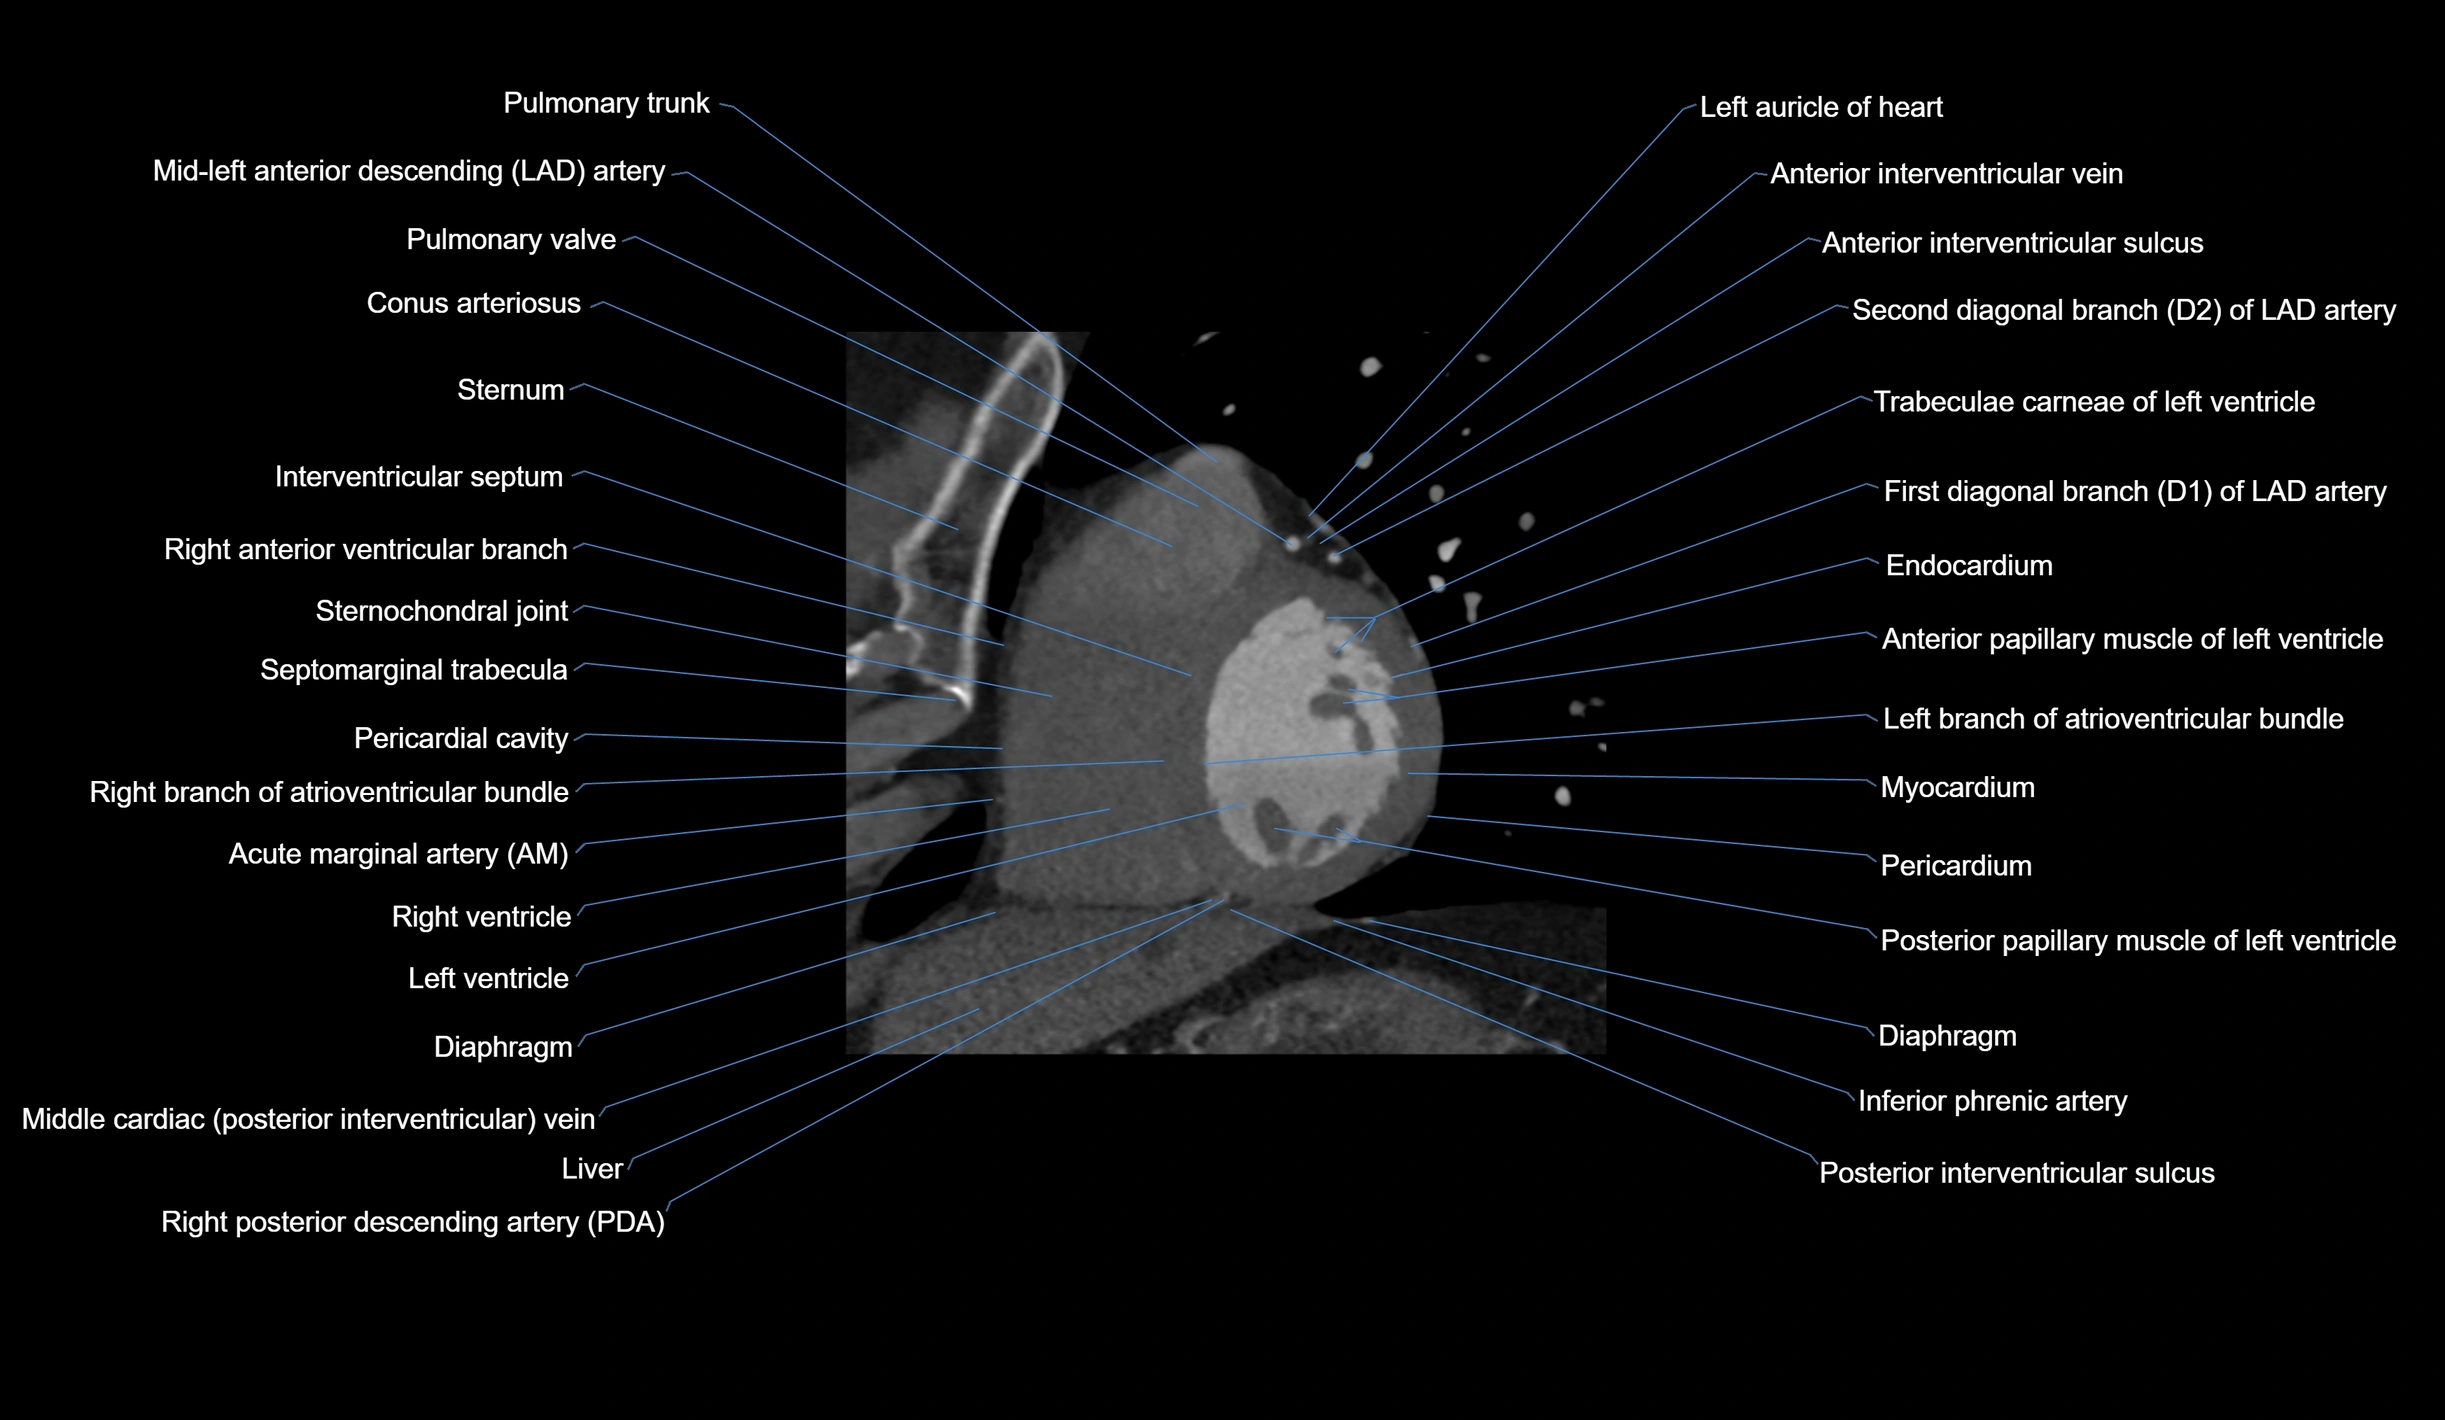

CT Appearance

Non-contrast CT (Calcium Scoring):

-

AM artery visualized for coronary calcium scoring

Calcified plaques appear as hyperdense foci; scored with Agatston method

CT Coronary Angiography (CCTA):

Best non-invasive modality for acute marginal artery visualization

Shows origin, course along the acute margin, and right ventricular branches

Detects stenosis, occlusion, calcified and non-calcified plaques, aneurysm, or anomalous course

Multiplanar reformats and 3D reconstructions help in pre-PCI and surgical planning

Critical for assessing right ventricular infarction risk in RCA disease

MRI image

CT images